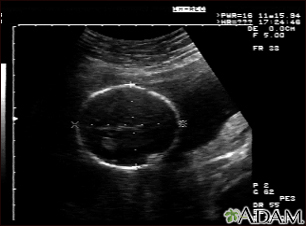

Ultrasound, normal fetus - head measurementsBackUltrasound, normal fetus - head measurementsThis is a normal fetal ultrasound performed at 19 weeks gestation. Many health care providers like to have fetal measurements to verify the size of the fetus and to look for any abnormalities. This ultrasound is of a head measurement, indicated by the cross hairs and dotted lines. E-mail FormEmail ResultsName:Email address:Recipients Name:Recipients address:Message: